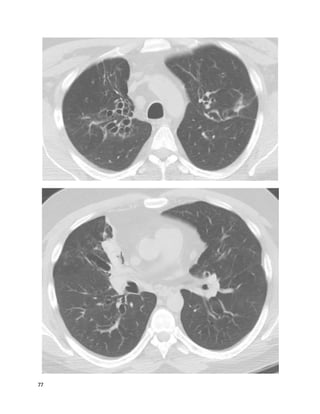

John, 33, is referred to you by his primary doctorfor bronchiectasis. John has had

recurrent respiratory infections since graduating high school. He takes inhaled

albuterol as needed, which in practice is never, becausehe does not perceive a

benefit. His symptoms of episodic cough, dyspnea, and infections wax and wane

unpredictably, but are progressing overall. Exam and vitals reveal distant breath

sounds with some rhonchi, and are otherwise normal. A thorough occupational /

14

inhalational history is negative. As you consider beginning an extensive workup

for unexplained bronchiectasis, you examine the test results below.

We feelthat C is the best answer.

Mounier-Kuhn syndrome, or congenital tracheobronchomegaly, is a rare inherited

disorder of cartilage formation resulting in enlargement of the C-rings in the

segmental bronchi and trachea. More distal bronchial structures are normal. (This

is in contradistinction to Williams-Campbell syndrome, in which central airways

are normal but distal airways are dilated.) The diagnosis is readily made on a CT

scan showing grossly enlarged central airways, especially with compatible

symptoms.

This patient's CT scanshows panacinar emphysema, with bullous disease worse at

the bases. Panacinar disease can merge with severe centrilobular emphysema to

create a nonspecific CT scan.